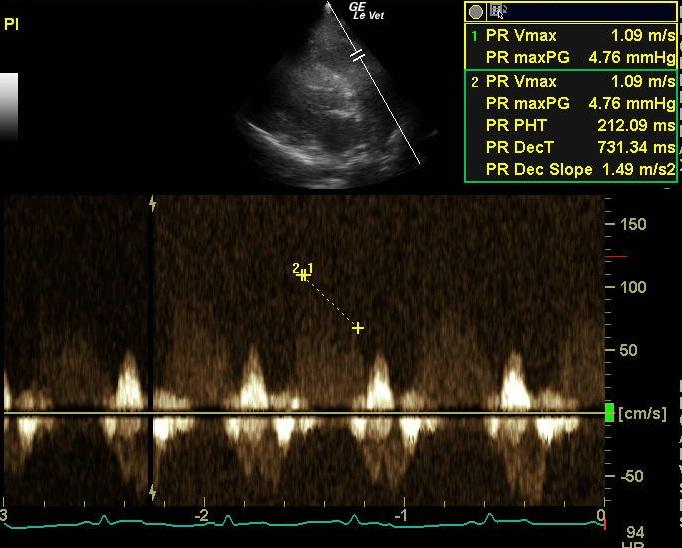

An 11-year-old MN Golden retriever was presented for evaluation due to two episodes of collapse and cyanosis. Additional history was that the patient was more lethargic than usual. Cardiac auscultation did not reveal any abnormalities and blood pressure was normal. Survey radiographs showed a mildly enlarged cardiac silhouette (VHS 11), prominent right ventricle, normal left atrial, and a normal lung pattern.